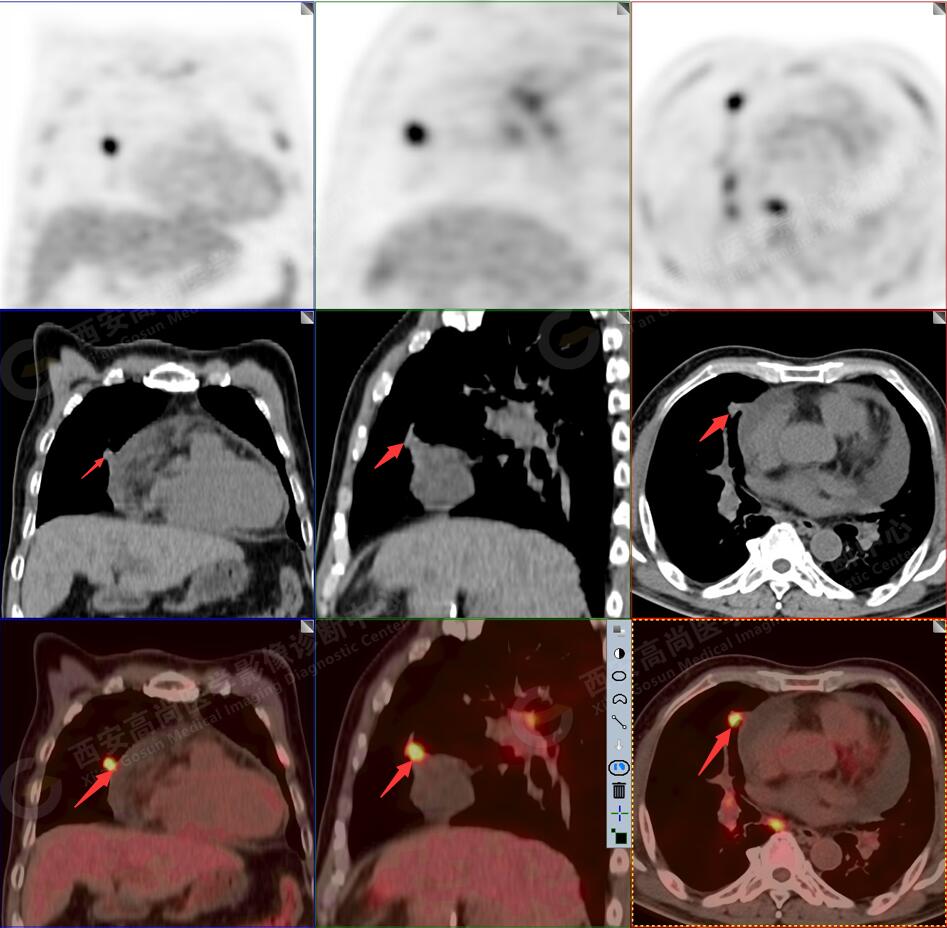

2.以下為全身多發(fā)轉移灶

3.右側頸部(Ⅱ-Ⅴ區(qū))、右側腋窩區(qū)、右側肺門及縱隔(1R、1L、2、4、6、7組)、肝門區(qū)多發(fā)腫大淋巴結,呈不同程度異常增高,均考慮為淋巴結轉移。

4.肝S4、8段團塊狀及結節(jié)狀低密度病變,以S4段病變?yōu)橹?,呈不同程度FDG代謝異常增高,考慮為肝多發(fā)轉移。